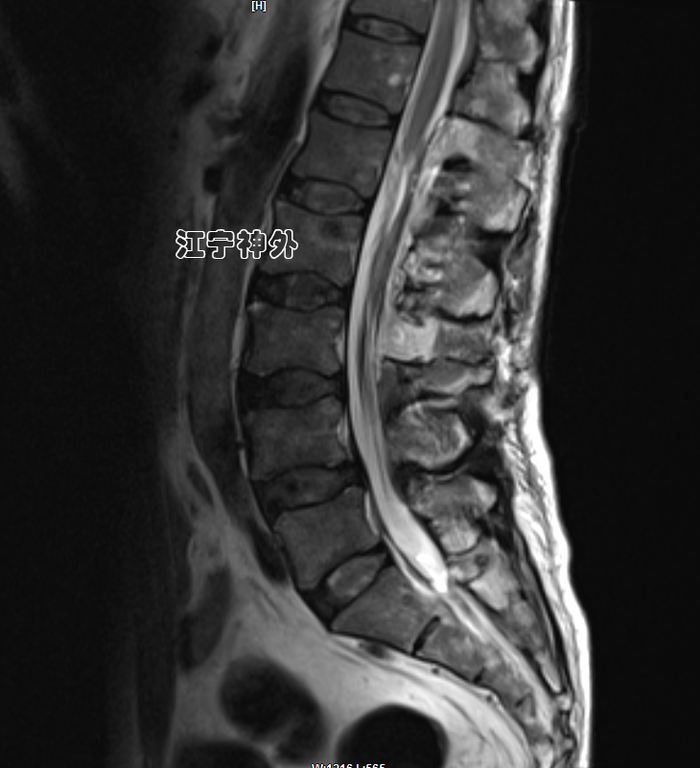

病例1:中年男性,因左侧臀部疼痛1年余,加重2月,在当地医院磁共振检查发现椎管肿瘤,经当地医生推荐,来到南京医科大学附属江宁医院神经外科郑学胜主任门诊就诊。

郑主任阅片发现,肿瘤位于胸10水平,属于髓外硬膜下病变,增强不均匀,边界清晰,位于脊髓的左后,脊髓被推向右前方。